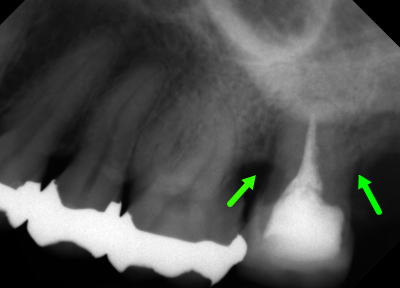

歯を移植した症例の画像です。

赤丸部分にあった親知らずを第二大臼歯(矢印)の位置に移植しています。

移植後3ヶ月で歯の周りに骨が再生してきているのがわかります。

上記は歯の移植画像です。

移植歯の利点は、成功すれば完全に自然な形で再生できます。